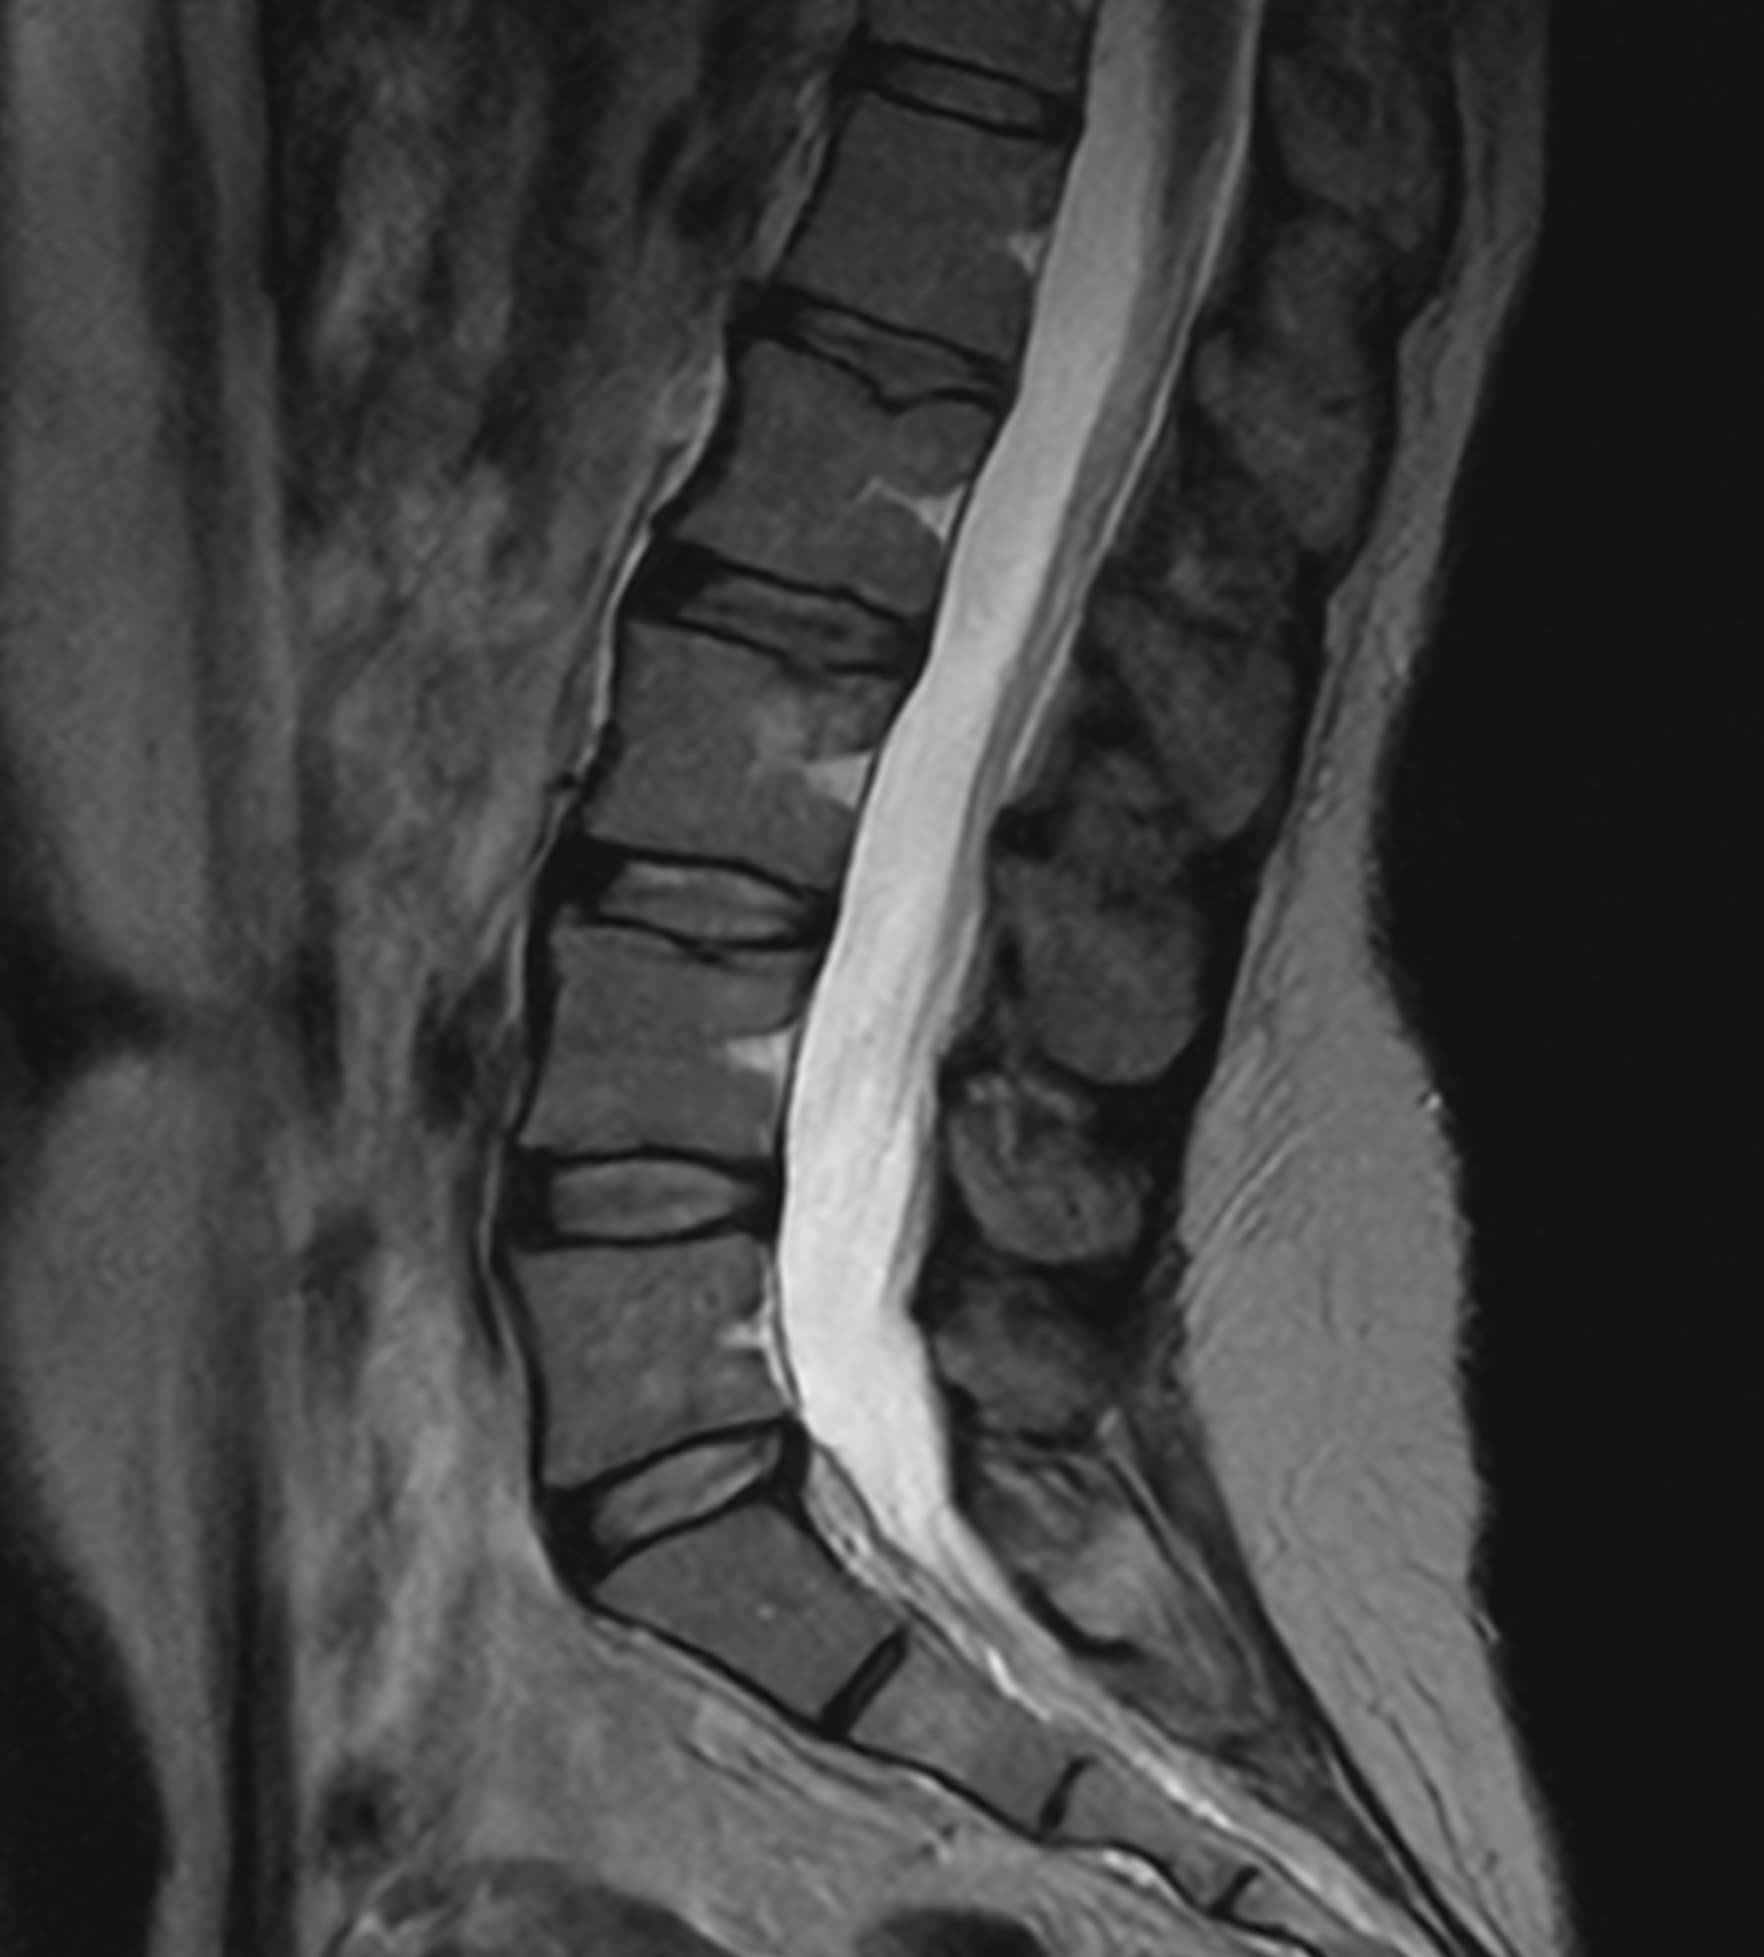

Δείτε πραγματικά παραδείγματα του SwiftMR™ σε διάφορα συστήματα MRI και ανατομικές περιοχές

Scan time 03:14

Scan time 02:07

Scan time 03:08

Scan time 1:12

Scan time 04:53

Scan time 1:46